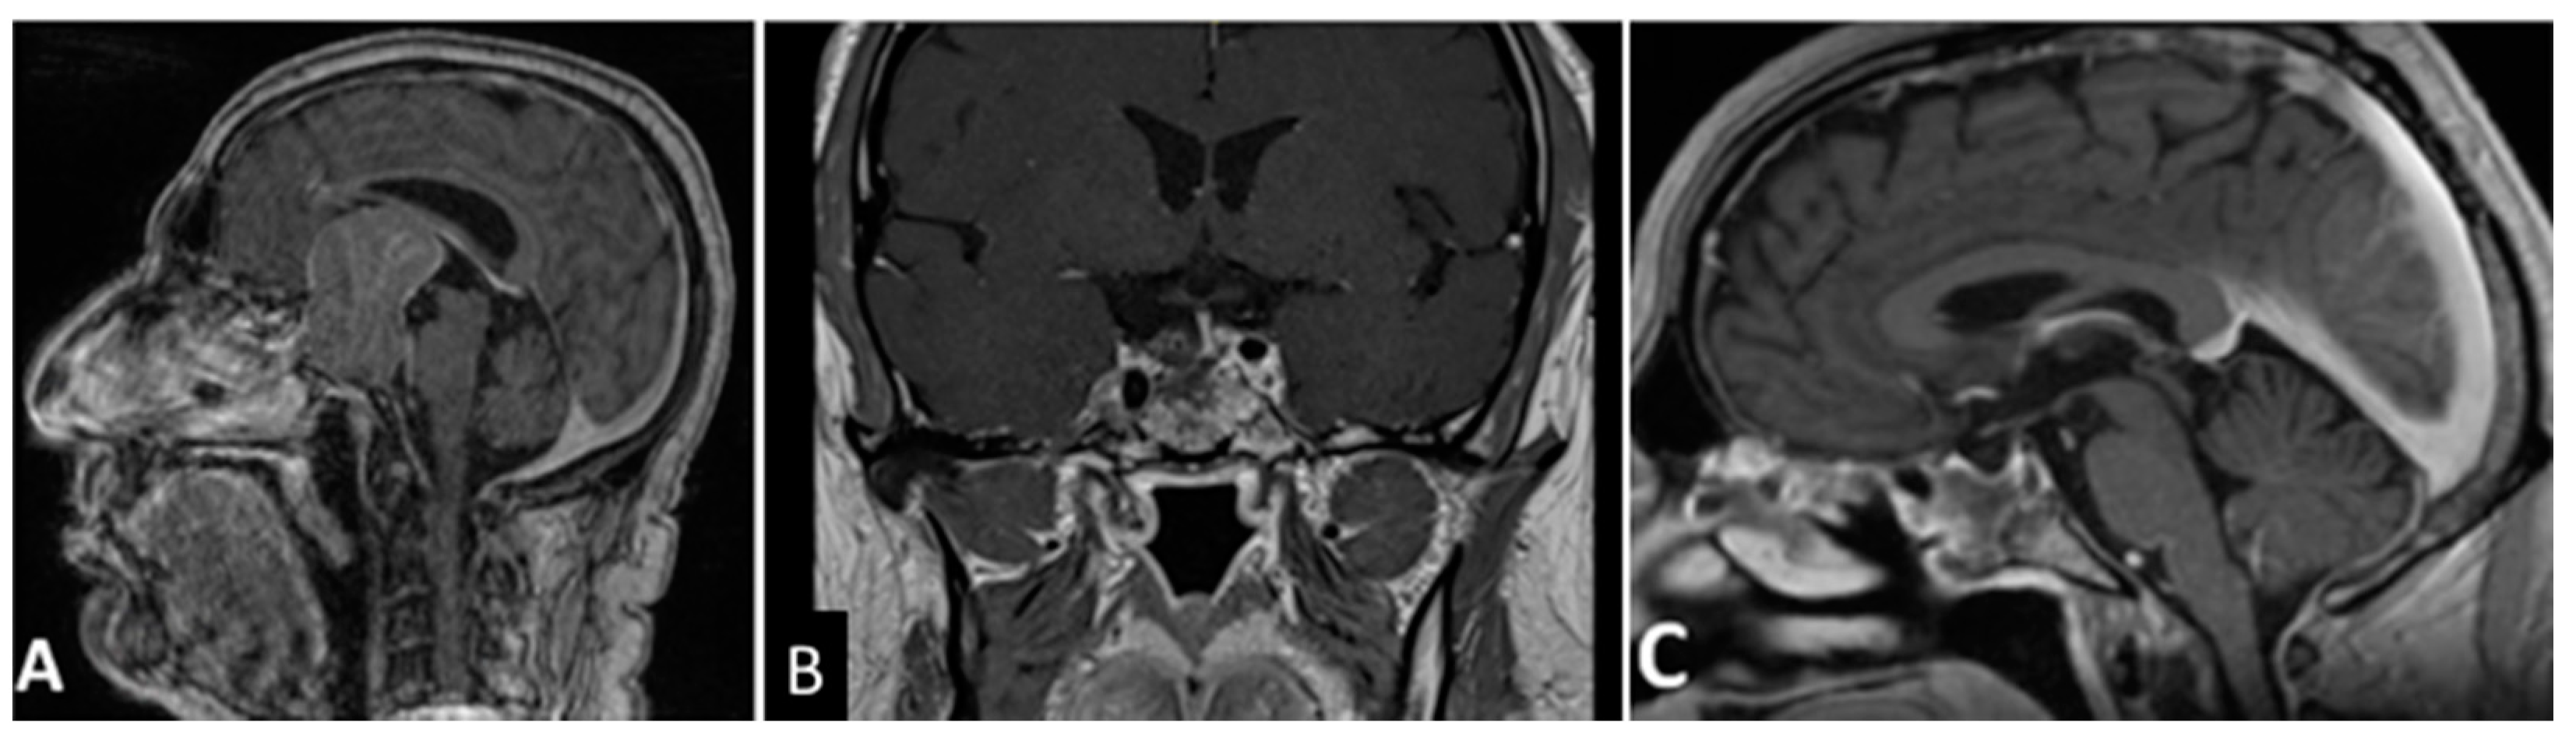

- Chibbaro, S.; Ganau, M.; Gubian, A.; Scibilia, A.; Todeschi, J.; Riehm, S.; Moliere, S.; DeBry, C.; Goichot, B.; Proust, F.; et al. The Role of Endoscopic Endonasal Approach in the Multimodal Management of Giant Pituitary Adenoma: Case Report and Literature Review. Asian J. Neurosurg. 2018, 13, 888–892. [Google Scholar]